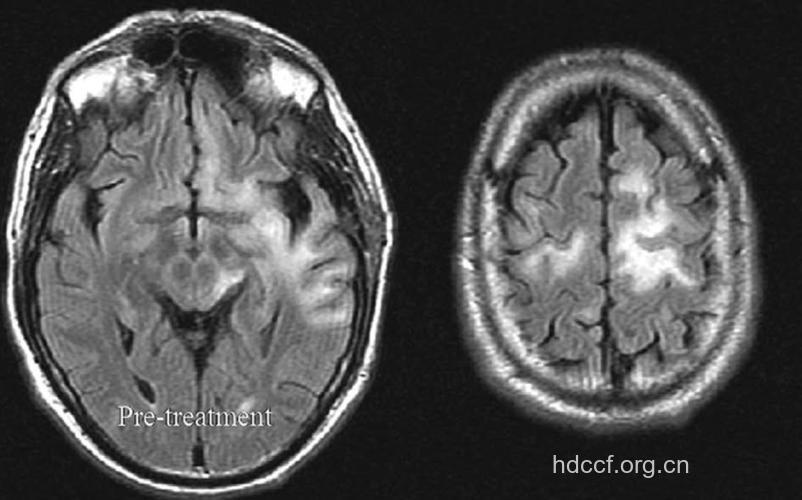

2、CSF检查正常;EEG显示特异的弥漫性或局灶性慢波。CT可见白质内多灶性低密度曲,无增强效应;MRI可见T2均质高信号、T1低或等信号。